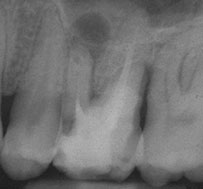

Breakage of endodontic files during treatment can result in serious complications and jeopardize the outcome of treatment. When using nickel-titanium (Ni-Ti) files, prevention of file breakage is complicated by the fact that these files rarely demonstrate visible evidence of cyclic fatigue and torsional stress and do not show wear before breakage.1 In the event that a file does break, removal can be difficult due to anatomical considerations, and the long-term prognosis of the tooth can become guarded.

An unfinished root canal will eventually cause many problems. The most common complication is that the tooth will begin to cause pain. There is also a risk that the tooth may fracture or cause a potentially dangerous swelling of the gum.

The greater the amount of uncleaned and unfilled canal space that remains after a root canal procedure, the greater failure rate. The challenge for clinicians is to decide to what point endodontic obturation should be directed in the given procedure. Cleaning, shaping and obturating less than the entire root canal space has the potential to or certainly could leave uncleaned and unfilled space, especially if the root is obturated to levels determined by arbitrary anatomic averages and not the true apical foramen.

Root canal overfills occur when a dentist is obturating (filling) a root canal. If the gutta percha(canal filling material) extrudes out the end of the root it is called an overfill. Sometimes, the gutta percha may have slipped through because it was not of sufficient diameter to bind at the apex. If a guttapercha that is too small is used, it can slip thru the tiny apical foramen (a hole at the tip of the root) and the resulting over fill may or may not form good seal . If the gutta percha does not adequately obturate (seal) the apex, then bacteria can repopulate any left over space. This bacterial colonization is most likely the actual cause of most endodontic failures associated with overfills.